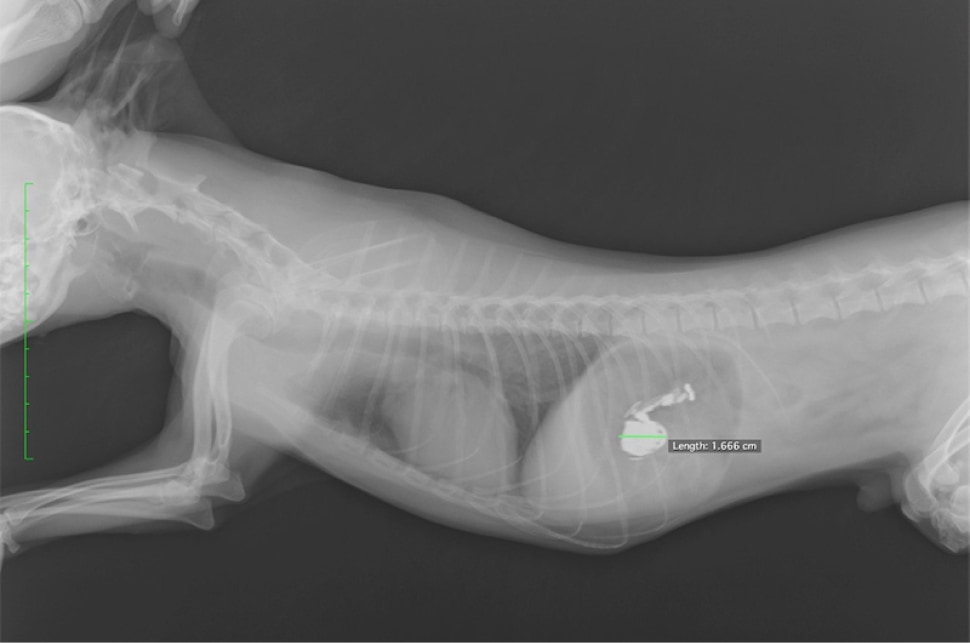

診断・治療

超音波検査から小腸で腫瘍による腸閉塞、また、それに伴い腸に穴が開いている(腸穿孔)が確認されました。物理的な閉塞ため、閉塞部位の切除が必要となるため外科手術による切除を実施しております。術後は下痢が認められるも食欲が改善し、嘔吐もなくなっております。

解説

猫の腸閉塞は、腸内の物質が正常に移動できなくなる状態で、異物の摂取、腫瘍、腸のねじれ(腸捻転、腸重積)などが原因で発生します。主な症状には、嘔吐、食欲不振、腹痛、元気消失、腹部の膨満感が見られ、長期に渡ると腸穿孔(腸に穴があくこと)を引き起こします。特に、嘔吐が続く場合は緊急性が高いです。診断には、身体検査や画像診断(X線や超音波)が用いられます。治療は通常、手術や内視鏡によって閉塞を解除し、必要に応じて腸の修復や異物の除去を行います。早期の発見と治療が予後に大きく影響します。